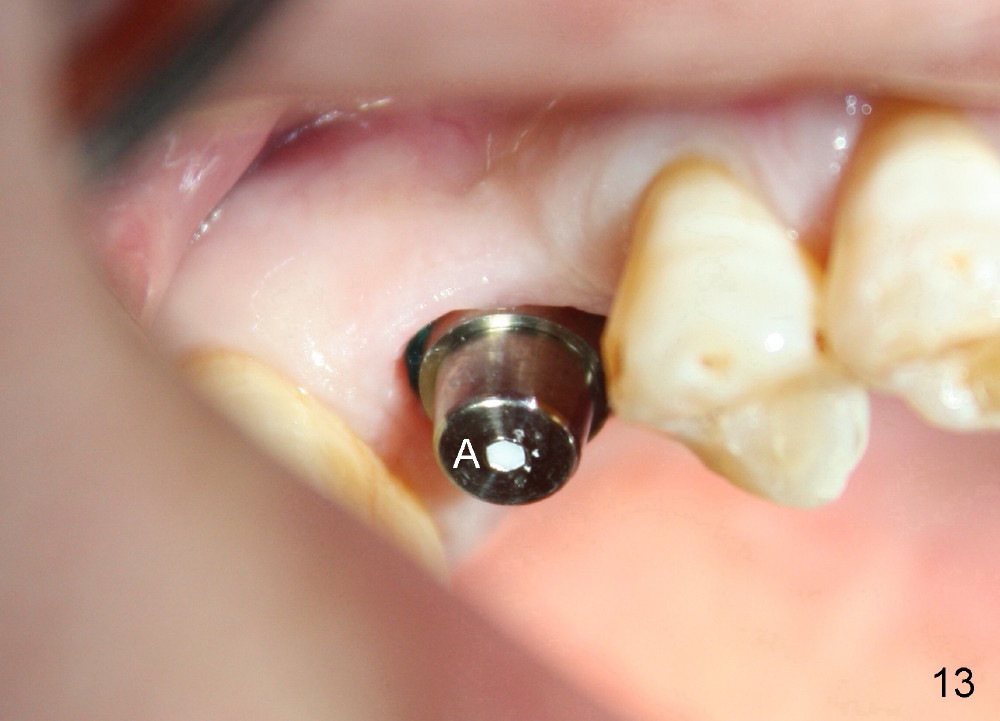

Following local anesthesia, the failing implant is removed without resistance. The sinus floor is present. The lateral walls are intact, although probably short. A series of rounded tapered osteotomes (2-5 mm in diameter) are used for sinus lift at the depth of 14 mm. A 4.5x14 mm tap is inserted (Fig.10). One more carpule of Lidocaine is administered. A 6x14 mm implant is placed with torque more than 60 Ncm without additional bone graft (Fig.11). A 6-month postop PA confirms osteointegration (Fig.12). An abutment is placed (Fig.13) for a definitive crown (Fig.14). PA taken 6 months post cementation shows that bone density mesial to the implant increases (Fig.15 <).